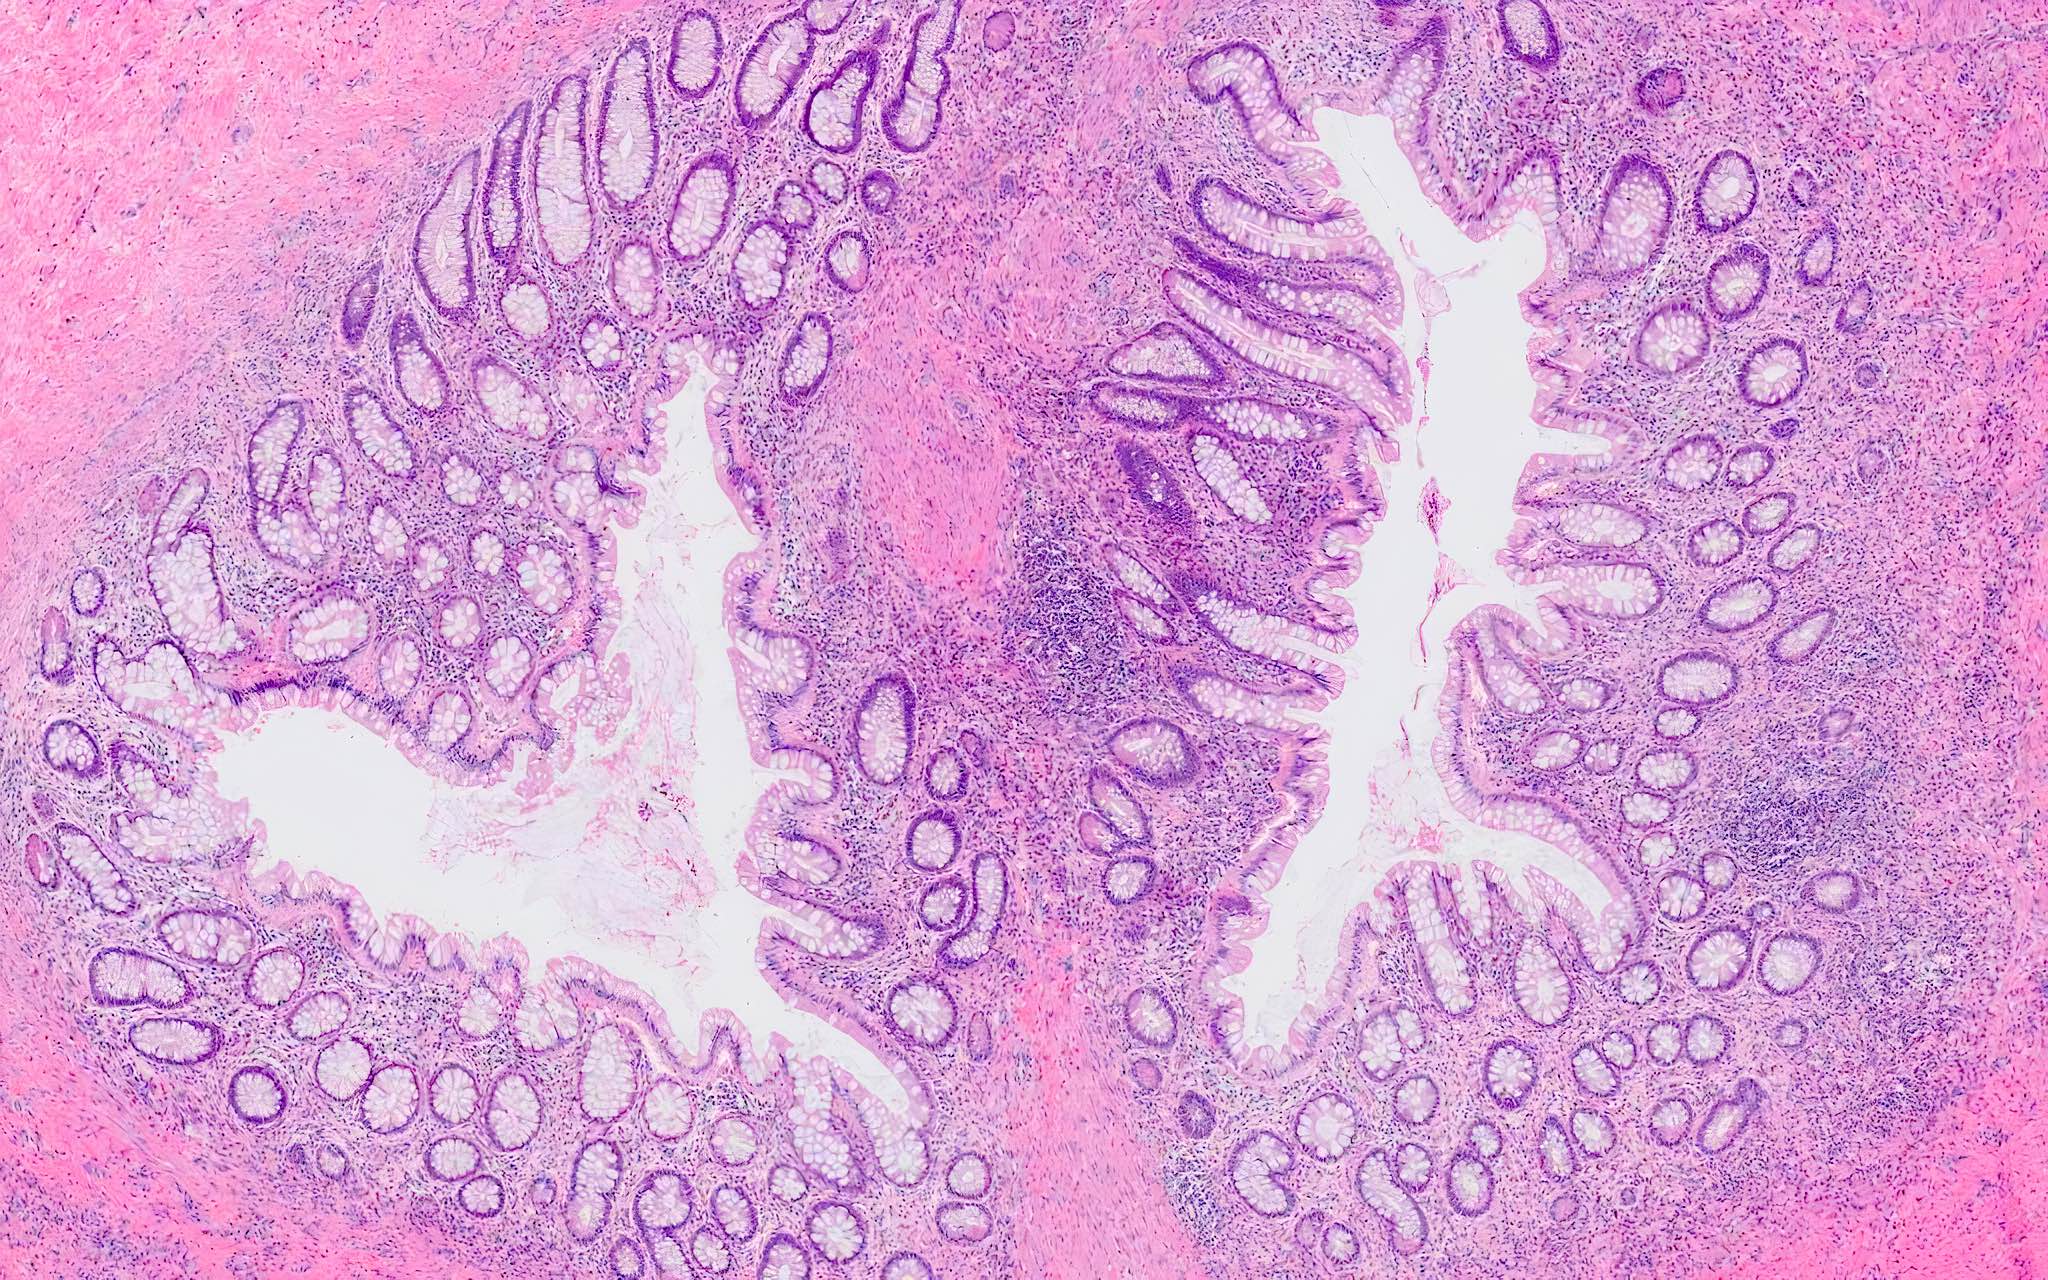

Microscopic (histologic) description

- Mucosa may be normal to markedly abnormal

- Expansion of lamina propria by lymphoplasmacytic infiltrate (more prominent in basal half)

- Lymphoglandular complexes, mucin depletion, focal Paneth cell metaplasia (in chronic cases) may be seen (J Clin Gastroenterol 2004;38:S11)

- Muscularis mucosa extends towards surface between elongated crypts

- Shortening of the affected bowel and hypertrophy of circular muscle layer (myochosis) leads to exaggerated mucosal folds (Am J Surg Pathol 1991;15:871)

- Some cases can show lamina propria fibrosis, crypt elongation on the tips of prominent mucosal folds, like mucosal prolapse syndrome in rectum and anus (J Clin Gastroenterol 2008;42:1137)

- Hemosiderin deposition in submucosa may be seen (StatPearls: Diverticulosis [Accessed 21 April 2022])

- Can mimic inflammatory bowel disease

- Hyperplasia of lymphoid aggregates is one of the earliest signs of diverticulitis

- Cryptitis, crypt abscesses, peridiverticular abscess and fistulas may be superimposed on this background in acute diverticulitis

- Tracking abscesses can spread longitudinally or circumferentially and can cause diverticular colitis

- Persistent localized inflammation can lead to phlegmon which is a thickened, firm segment of bowel wall that can lead to strictures and acute or subacute large bowel obstruction (Best Pract Res Clin Gastroenterol 2002;16:543)

Microscopic (histologic) images

Contributed by Bindu Challa, M.D. and Martha M. Yearsley, M.D.